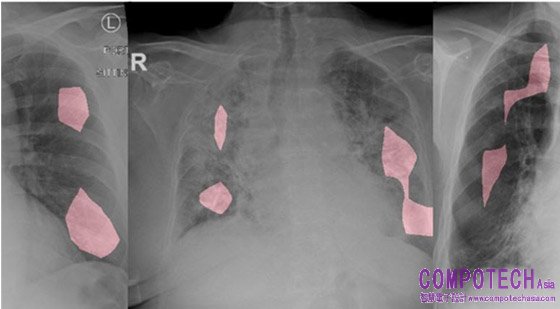

用GenSynth識別來自不同COVID-19病例的CXR圖像及其相關的關鍵因素(紅色部分) (圖片來源,arm.com)

DarwinAI的COVID-Net由1x1卷積層和深度卷積層組成,是一種高效的微架構設計,有COVIDNet-CXR4-A,COVIDNet-CXR4-B和COVIDNet-CXR4-C三個模型共設計人員參考,每個模型均使用GenSynth平臺構建,在性能與效率之間權衡,均能對三種結果進行預測:

1. 無感染(正常)

2. 非COVID-19感染(例如,非COVID19病毒,細菌等)。

3. COVID-19病毒感染

其中,COVIDNet-CXR4-C代表了最緊湊的模型,能夠在嵌入式環境中運行良好。透過使用ARM的Cortex系列處理器,在硬體設施不夠完善的偏遠地區發揮較大的作用。